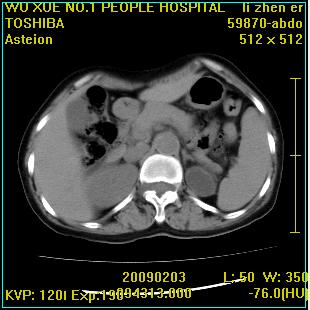

标题: CT18564:女,57岁,无不适,体验B超提示肾积水等 [打印本页]

标题: CT18564:女,57岁,无不适,体验B超提示肾积水等

左侧多囊肾可能。

左肾及左输尿管上端结石,左肾重度积水并左肾萎缩(不排除左肾先天性发育不良)。

左输尿管上端结石,左发育不良性多囊肾并积水;

右肾代偿性增大并肾盂积水,脾大。

此患都左肾呈囊性变,边缘有高密度钙化,还是考虑结核吧.